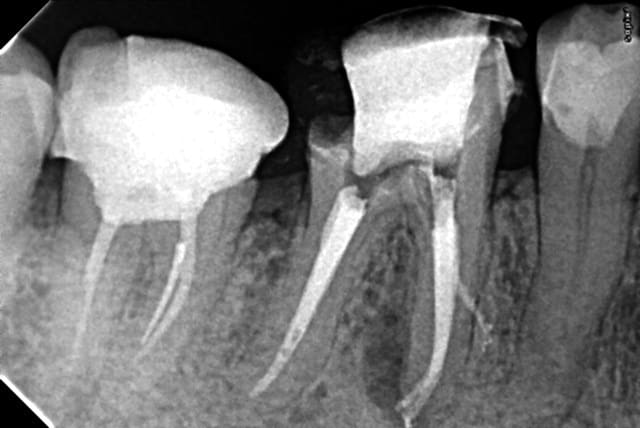

Il ne faut pas forcer pour extraire simplement insérer l'élévateur au bon endroit (enfin bon je l'ai bien dé calottée la couronne ( mouvement de l'avant bras proche de celui qu'on fait quand on essaye de faire une gamelle au baby foot) avant de séparer les racines mais des fois tout vient en meme temps lol !) . C'est au moment de soulever la racine distale que j'avais mobilisée qu'elle s'est fait la malle. -)

cette racine me parait très bien ou elle est.

Pourquoi la chercher? (rapport avantages inconvénients)

Je la laisserais bien à sa place (sauf si la pulpe était nécrosée bien sûr)et j'attendrais....

ça risque de faire un bel implant naturel et....c'est tout

Rendez vous dans un an en urgence pour l'extraction. Que j'adresserais au stomato. -)